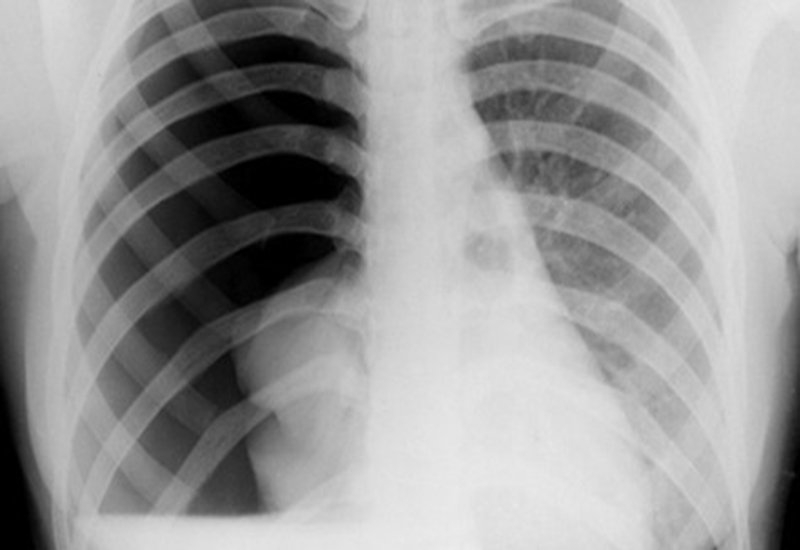

Nguyên nhân tràn khí màng phổi là gì?

Tràn khí màng phổi là tình trạng bị xẹp của một hay cả hai lá phổi do không khí xâm nhập vào khoang màng phổi. Chính lượng không khí này ép vào phía ngoài phổi và khiến cho phổi xẹp xuống. Khoang màng phổi chính là khoảng không gian nằm giữa các lá màng phổi, có lớp màng bao bọc quanh các lá phổi của con người. Trong thực tế con người có thể gặp phải tình trạng tràn khí màng phổi tự phát và tràn khí màng phổi tái phát.

Nguyên nhân tràn khí màng phổi là gì? 1 Tràn khí màng phổi là bệnh lý khá nguy hiểm